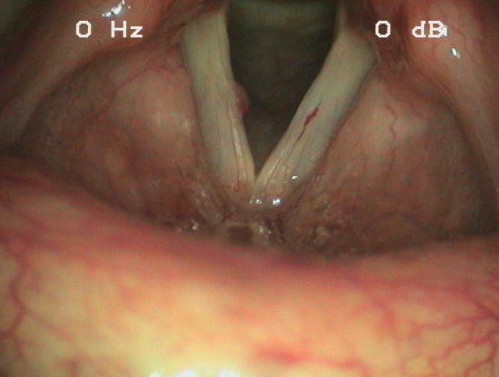

Eine 36-jährige klassische Sängerin klagt über Unsicherheiten beim Singen und über eine Rauhigkeit ihrer Stimme. Einen genauen Zeitpunkt des Beschwerdebeginns kann Sie nicht nennen. Die Problematik besteht jedoch seit mindestens einem halben Jahr.

Die Patientin fürchtet, dass die Ausübung ihres Berufes gefährdet ist.